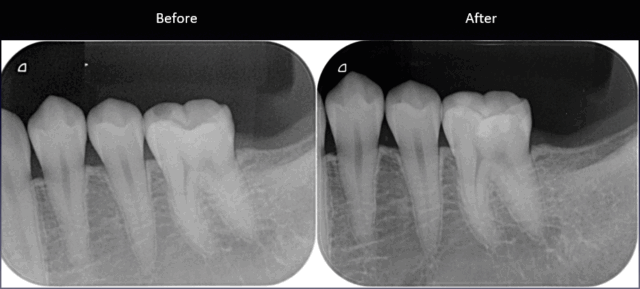

before

after

| 通院回数・期間 | 1回〜3回 |

| 処置内容 | 右下6番(セラミックインレー)7番(ダイレクトボンディング)を治療 |

| 今回の施術費用 | ¥33,000〜110,000 |

メリット

歯を削る量を少なくできる。歯に直接詰め物をつけることができる。ピッタリ詰めれる。

デメリット

奥歯で器具が入りにくい場所や、大きい虫歯治療には適応できない場合がある。